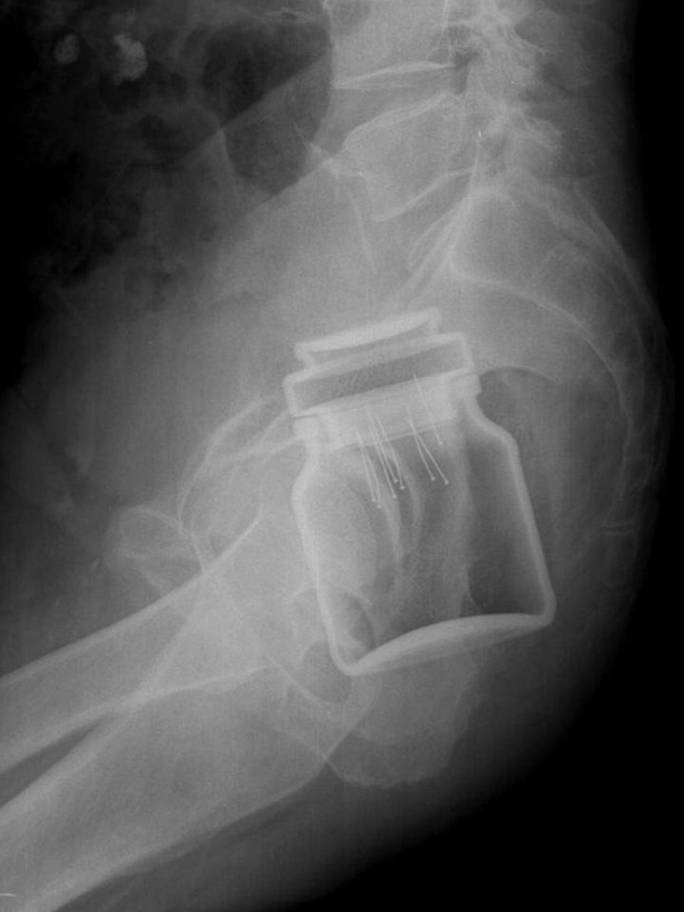

人間は本当に奇妙な生き物であり、信じられないほど奇妙なことが私たちに起こる可能性があります。これらの X 線写真は、すべてを見てきたと思っている人でも衝撃を受けるでしょう。

Radiologi so tako že precej navajeni, da na rentgenskih posnetkih vidijo čudne stvari in nekatere izmed teh, ki smo jih za vas zbrali v galeriji, jih sploh niso presenetile. Tukaj je 15+ odštekanih in na trenutke šokantnih rentgenskih posnetkov.